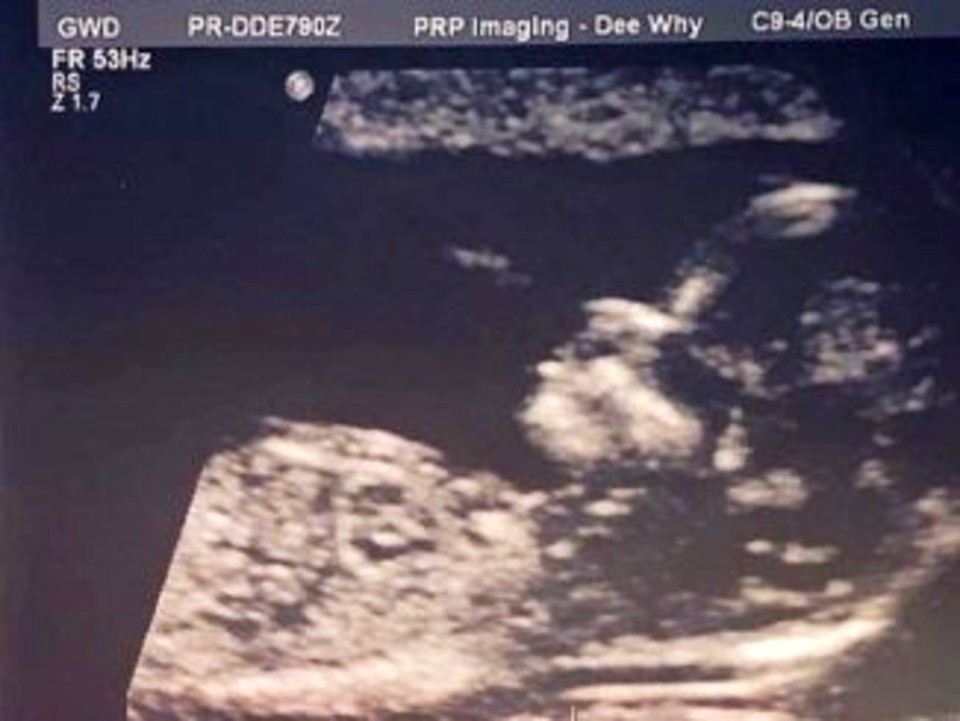

An ultrasound X-ray revealed that babies have hair just a few weeks after conception, despite the fact that it typically takes infants a year or two to acquire their hair accessories.

Little Alexis already has gorgeous shoulder-length hair six months after giving birth. When her parents first saw the ultrasound, they were concerned since she appeared to have hair on her forehead, back, and buttocks.

A gorgeous infant looks like this: